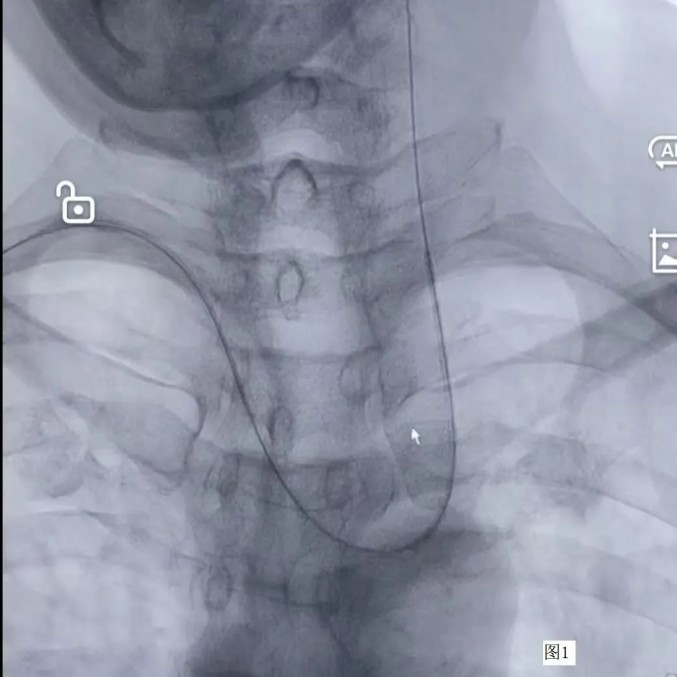

7月27日,患者“经桡动脉心脑血管同时造影术”在导管室进行。术中,神经外科一病房团队首先进行脑血管造影,心内科团队随后完成心血管造影。

经右侧桡动脉造影管顺利进入左侧颈总动脉